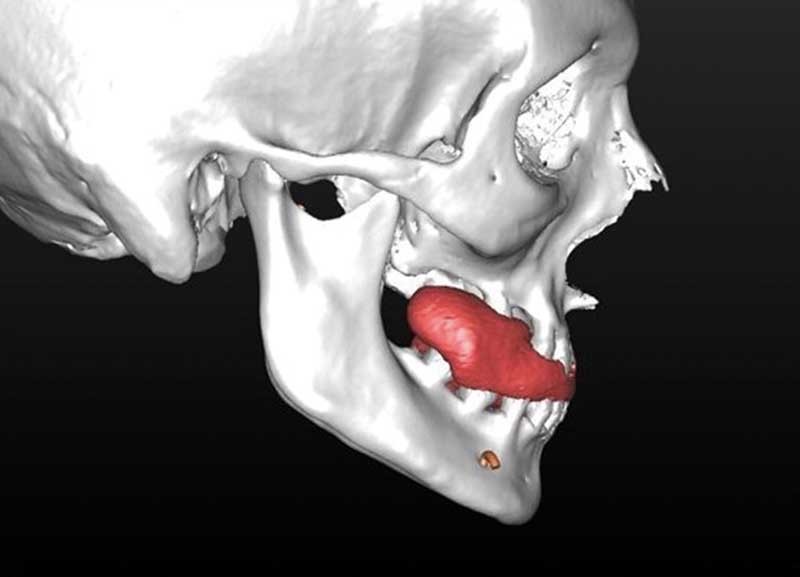

En cas d’hypo-divergence, qu’il s’agisse d’une classe II ou d’une classe III, la mandibule est stabilisée après avoir déterminé « l’espace libre d’innoclusion » (free way space) à l’aide d’une cale radio-opaque ou radio transparente (fig. 2 à 5).

– élaboration des images 3D en isolant des différents constituants anatomiques : crâne et maxillaire, mandibule, dents, dispositifs d’orthodontie, implants endo-osseux et prothèses conjointes éventuelles, etc.